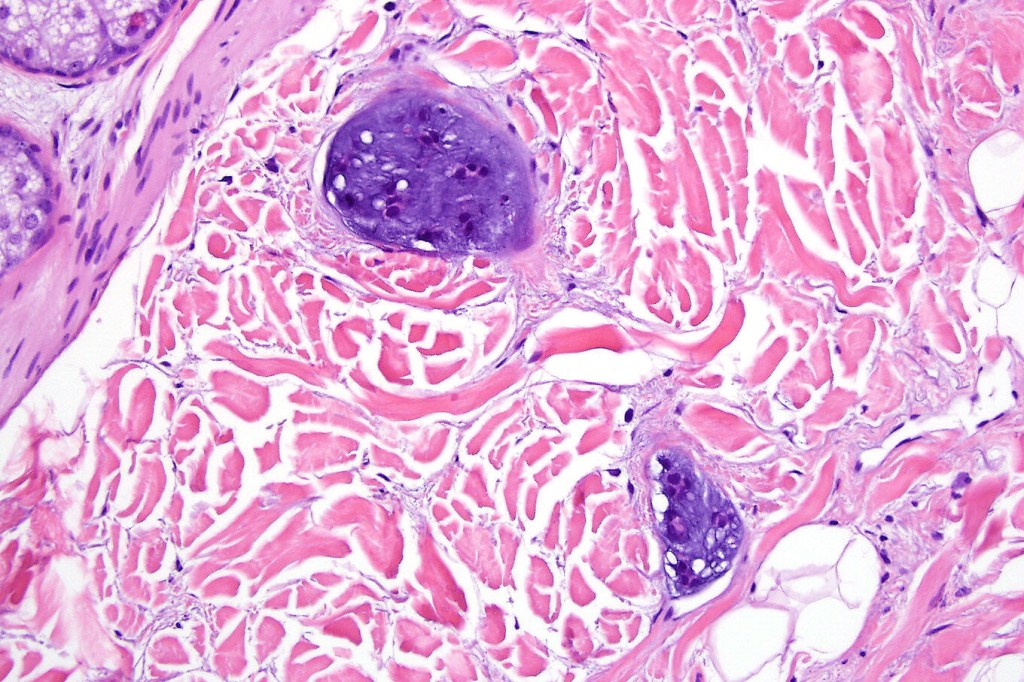

•Well circumscribed unencapsulated, nodular/multinodular silhouette composed of an admixture of epithelial & mesenchymal elements

•Often intensely basophilic due to mucinous deposits

•Mixed epithelial component including nests & cords of epithelium with abundant, eosinophilic cytoplasm & small vesicular nuclei

•Glandular differentiation sometimes showing apocrine differentiation

•Ductal differentiation

•Cribriform/retiform appearance occasionally evident

•Chondroid foci